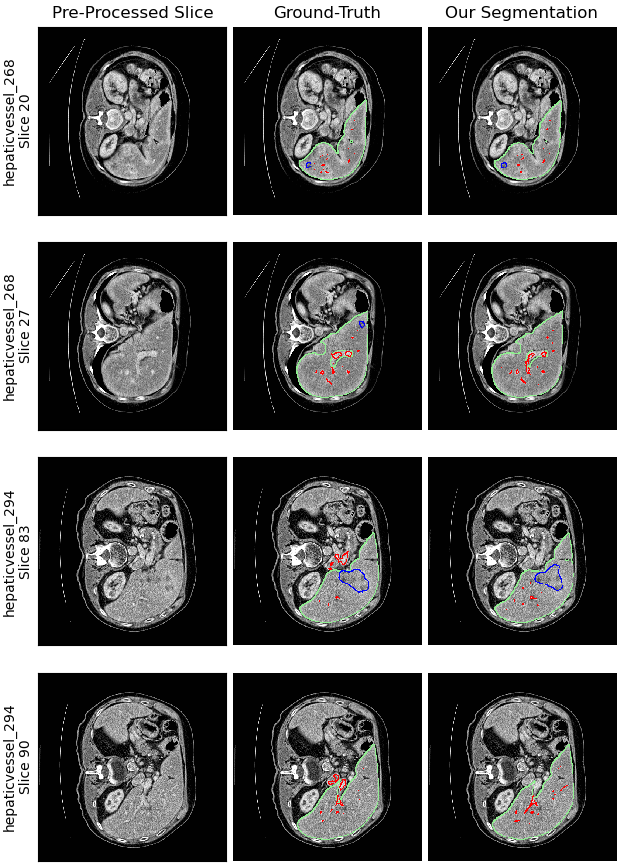

Figure 12 demonstrates a comparison between “Our Segmentation”, representing the combined results of the three optimally trained ConvNets, and the “Ground-Truth” masks. Specifically, for volume hepaticvessel_268, the liver segmentation exhibits near-perfect alignment in slices 20 and 27.

For the liver parenchyma segmentation, we can confidently mention that the liver ConvNet has successfully segmented the liver, reaching ground-truth precision.

The ConvNet’s performance in tumor segmentation varies across different slices: it performs well in slice 20, yet fails to detect a small tumor in slice 27. Conversely, in the case of vessel detection, while the ConvNet overlooks some minor vessels in slice 20, it excels in slices 83 and 90, capturing all the vessels effectively—surpassing even the ground-truth mask in accuracy.

Focusing on slice 83 within the hepaticvessel_294 volume, the tumor segmentation ConvNet successfully identifies and accurately delineates the tumor, demonstrating high recall. Similarly, the vessel ConvNet effectively captures all vessel tissues within the liver, suggesting its performance might exceed that of the original mask. However, vessels located outside the liver are not detected, a limitation imposed by the application of the liver mask. This observation highlights a notable insight: the impact of the liver mask on vessel detection varies based on their proximity to the liver. For instance, while vessels within the liver but outside the liver mask in hepaticvessel_268 are detected, those in hepaticvessel_294 that lie outside both the liver and its mask are missed. This differential effect underscores the complex interaction between the segmentation process and the anatomical positioning of the vessels. This could be attributed to the inter-variance of the dataset that we have, where some liver masks would have considered the inner vessels to be part of the liver, while others, such as the case of hepaticvessel_268, consider vessels outside of the liver mask.